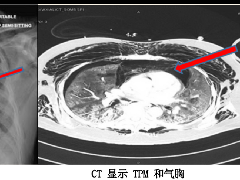

纵隔大细胞神经内分泌癌1例CT影像

纵隔大细胞神经内分泌癌1例CT影像  张力性纵隔气肿影像表现及严重度分级